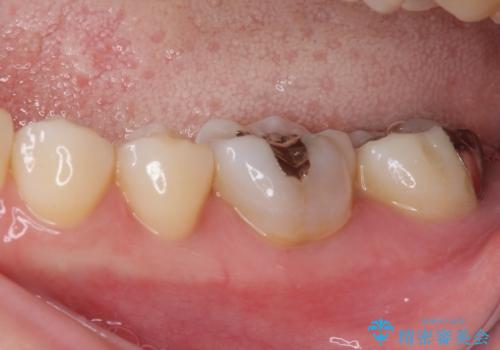

奥歯が痛い 保険治療後に症状が発現した歯のむし歯治療

- 近医にてむし歯治療を行った後に痛みが出たとのことで来院された患者様です。

左下奥歯は術後から咬合時の痛みが発現し、来院時には脈を打つような痛みが認められました。

診察の結果、神経を取り除く必要があると判断されたため根管治療を行いました。

その後、左上の奥歯にも咬合時の痛みが認められ、レントゲン写真より歯内の神経が失活していることが分かりました。

2歯ともに根管治療を行い、その後はオールセラミッククラウンにて補綴治療を行うこととしました。